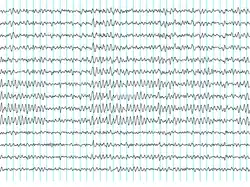

The history of brain-computer interfaces (BCIs) starts with Hans Berger's discovery of the brain's electrical activity and the development of electroencephalography (EEG). In 1924 Berger was the first to record human brain activity utilizing EEG. Berger was able to identify oscillatory activity, such as the alpha wave (8–13 Hz), by analyzing EEG traces.

Berger's first recording device was rudimentary. He inserted silver wires under the scalps of his patients. These were later replaced by silver foils attached to the patient's head by rubber bandages. Berger connected these sensors to a Lippmann capillary electrometer, with disappointing results. However, more sophisticated measuring devices, such as the Siemens double-coil recording galvanometer, which displayed voltages as small as 10−4 volt, led to success.

Berger analyzed the interrelation of alternations in his EEG wave diagrams with brain diseases. EEGs permitted completely new possibilities for brain research.